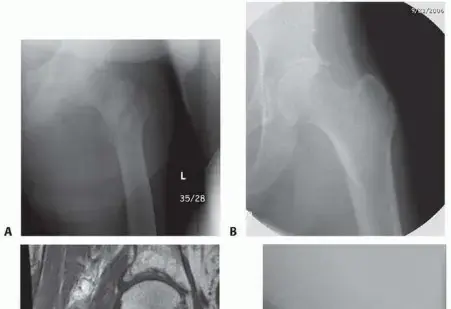

الفحوصات التصويرية (Imaging Tests):

- الأشعة السينية (X-rays):

- هي الفحص الأول والأساسي لتشخيص كسر الورك.

- تُظهر الأشعة السينية صورًا مفصلة للعظام وتكشف بوضوح عن وجود الكسر وموقعه ونوعه ومدى إزاحة العظام المكسورة.

- يتم التقاط صور متعددة من زوايا مختلفة لتقييم الكسر بشكل كامل.

- الأشعة المقطعية (CT Scan):

- في بعض الحالات المعقدة، أو عندما لا تكون الأشعة السينية كافية لتوضيح تفاصيل الكسر، قد يطلب الدكتور هطيف أشعة مقطعية.

- توفر الأشعة المقطعية صورًا ثلاثية الأبعاد للعظام، مما يساعد على تقييم مدى تعقيد الكسر، عدد القطع المكسورة، وموقعها بدقة عالية، وهذا ضروري للتخطيط الجراحي.

- التصوير بالرنين المغناطيسي (MRI):

- نادرًا ما يُستخدم التصوير بالرنين المغناطيسي في الحالات الحادة لكسور الورك، ولكنه قد يكون مفيدًا إذا كان هناك اشتباه بوجود كسر خفي (كسر إجهادي أو كسر شعري لا يظهر بوضوح في الأشعة السينية)، أو لتقييم الأنسجة الرخوة المحيطة.